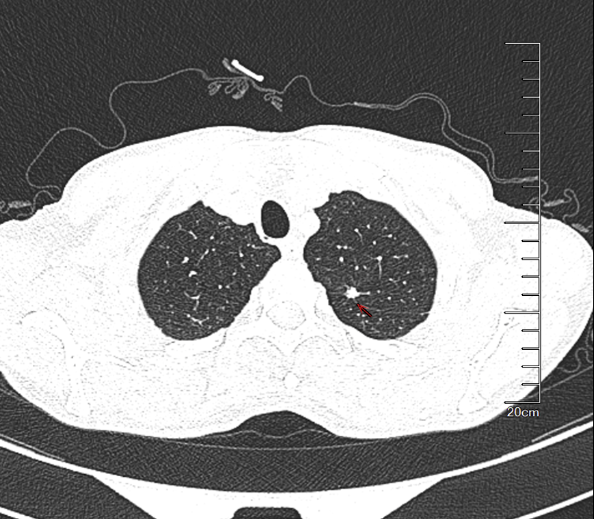

(5)、[2025-06-06]支气管镜(图1)并送检靶向病原微生物高通量测序(tNGS)(图2、图3、图4):如下图:

(6)、我院胸部CT:1、右肺上叶后段磨玻璃结节,密切随诊。(Lung-RADS 3);2、余肺内可见多发微小结节,随诊。(Lung-RADS 2)3、右肺中叶不张。右肺下叶背段少许支扩。4、升主动脉横径增宽,径约41mm。